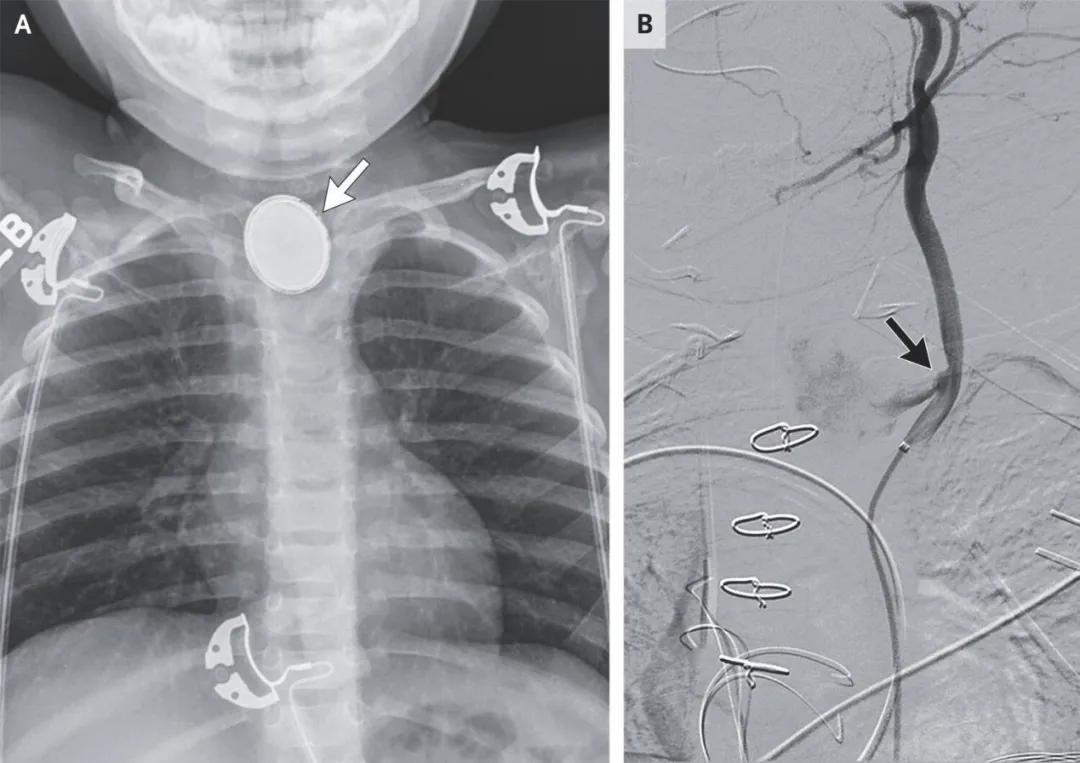

带孩子的爷爷奶奶注意了⚠️孩子误吞纽扣电池有多危险?不是取出来就没事,有的会突然呕血丧命!先来看两个案例: 案例一:一个月大的婴儿,家长发现吃不下去奶,同时呼吸困难,送往医院拍片子发现食道里面卡着一个纽扣电池。紧急做了胃镜,取出纽扣电池。胃镜检查并没有看到食道有什么损伤。但是在10个小时以后突然出现呕吐鲜血。紧急做了血管造影,发现食管和左颈总动脉之间因为纽扣电池的压迫已经造成了组织损伤,最终形成瘘管。动脉里的血穿过瘘管从食管喷出,紧急止血后转危为安。 案例二:2 岁幼儿,因误食异物住院,胃镜检查发现是一枚纽扣电池。同时发现被纽扣电池卡住的地方食管黏膜充血、肿胀,少量渗血,未见明显穿孔。住院一周好转后出院。出院 3 天后突发呕血,抢救无效身亡。尸检鉴定显示被纽扣掐住的食道与胸主动脉形成瘘管,血从主动脉涌向食管,最终引起窒息和出血性休克。 纽扣电池一旦卡在食管里,短时间内就可能持续放电,并产生强碱性腐蚀,迅速灼伤周围组织。 更可怕的是,有些孩子当时看起来没事,甚至已经出院,几天后却突然加重, 原因就在于电池造成的损伤并不会随着“取出”立刻停止,严重者会形成食管与大血管之间的瘘管,一旦破裂,就是致命性大出血。 婴幼儿误食纽扣电池后,往往不能清楚表达不适症状,只是哭闹、吞咽不适、咳嗽,很多家长会误以为是感冒、咽炎或普通肠胃不适,从而错过最佳处理时间。 所以要记住:只要怀疑孩子吞了纽扣电池,第一时间去医院,尽快拍X线,尽快处理。 即使已经取出,也一定要按医生要求复查、观察,千万别觉得“拿出来就安全了”。 还有就是类似于纽扣电池、硬币、圆珠笔等含有细小部件的物品平常一定要放在婴幼儿接触不到的位置。